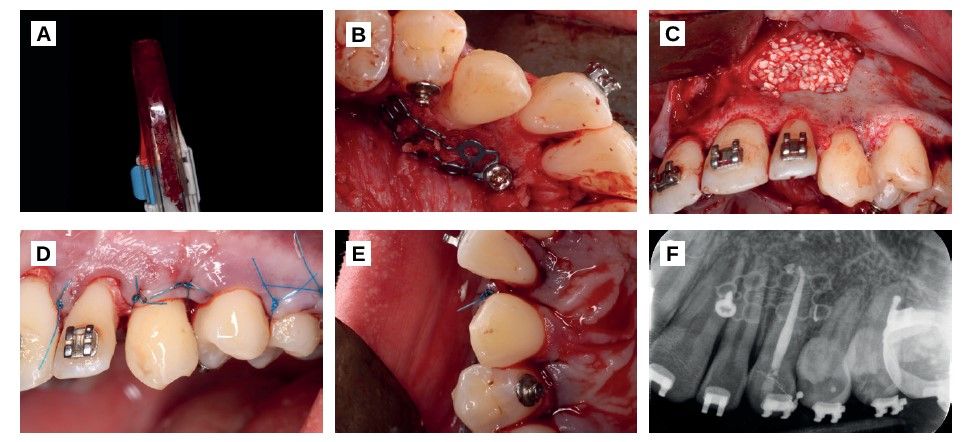

Both the anterior palatine nerve and the nasopalatine nerve were anaesthetized.

Intrasulcular incisions and a crestal incision were made in the edentulous space of the left upper canine (2.3). A vestibular flap was lifted at total thickness from the first left upper molar (2.6) to the contralateral lateral incisor (Figure 2). Using a round osteotomy drill number 8 from a hand piece, a vestibular bone window was made until the whole canine crown was exposed (Figure 2). The tooth was then loosened using two elevators, without exceeding the amelocementary limit to avoid damaging the periodontal ligament fibres (Figure 2).

The osteotomy was performed in the crestal region in order to make a surgical alveolus (Figure 2) with an anatomy similar to the future canine autotransplantation using surgical implant drills from the same business (Biomet 3i, Barcelona, Spain). A tooth exodontia was performed (Figure 2) and moved to the surgical alveolus (Figure 2). Guided bone regeneration was performed in the vestibular and palatal region of the same, both to surround the tooth in a favourable bone frame and to regenerate the vestibular defect that remained after the extraction of the canine.

After 2 weeks of the surgery, periapical X-rays were taken and a root canal of the canine was performed under absolute isolation (Figure 3).